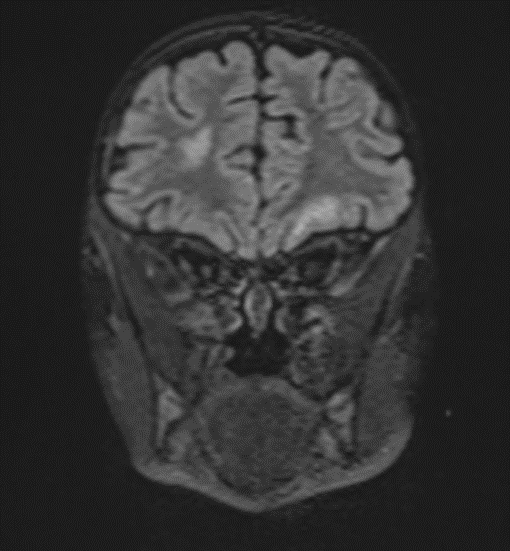

The changes observed are characteristic radiological markers appreciated on DWI, indicative of cytotoxic edema. The DWI changes are considered reliable early signs of acute toxic encephalopathy, specifically methotrexate-related leukoencephalopathy. Post-contrast MR images did not show any abnormal contrast enhancement.

Picture 4.